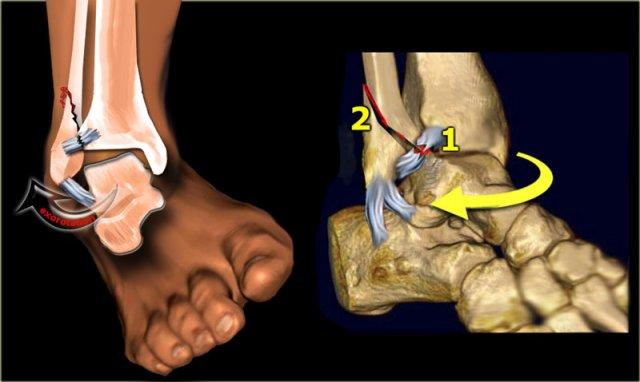

Weber A

Xảy ra dưới khớp chày mác, khớp này còn nguyên vẹn.

Theo Lauge-Hansen, đây là kết quả của lực khép tác động lên bàn chân ở tư thế sấp.

- Giai đoạn 1 – Lực căng lên các dây chằng bên ngoài dẫn đến đứt dây chằng

hoặc gãy giật (avulsion) mắt cá ngoài ở dưới khớp chày mác. - Giai đoạn 2 – Gãy chéo mắt cá trong.

Lưu ý rằng đường gãy xương mác có hướng ngang, vì đây là gãy giật (avulsion) hay gãy do lực kéo.

Đường gãy xương chày có hướng thẳng đứng hoặc chéo, vì đây là gãy do lực đẩy.

Stage 1

Các hình ảnh cho thấy gãy xương loại Weber A điển hình.

Tất cả đều là gãy xương giai đoạn 1.

Giai đoạn 2 cực kỳ hiếm gặp.

Chú ý hướng nằm ngang của các đường gãy.

Đây là các gãy xương kiểu giật đứt do kết quả của sự bong gân giật.

Stage 2

Giai đoạn 2 không phổ biến và dễ phát hiện.

Lực khép lớn hơn dẫn đến mắt cá trong bị đẩy ra theo chiều dọc hoặc chéo.

Giai đoạn 2 không vững vì vòng cổ chân bị gãy ở hai vị trí.

Lưu ý hướng nằm ngang của gãy mắt cá ngoài và hướng thẳng đứng của gãy mắt cá trong.

Những lực cực lớn hẳn đã đẩy bật mắt cá trong ra.